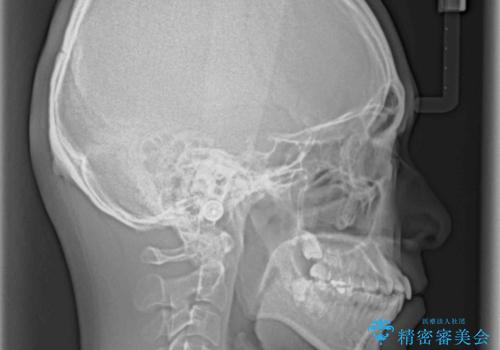

顎が左右にずれた咬み合わせ ハーフリンガルの抜歯矯正

- 口元の突出感を気にして来院された患者様です。

目立たない装置を希望され、上顎が裏側装置で下顎が表側装置のハーフリンガルを希望されました。

上下の顎骨が左右に大きくずれており、奥歯が交叉咬合となっていたため、ハーフリンガルよりも表側装置をおすすめしましたが、目立たない装置を強く希望されたため、治療期間が長期化することを前提に、ハーフリンガルにて抜歯矯正を行うこととしました。

裏側装置での交叉咬合改善は非常に困難なもので、頻繁に装置の脱落がありました。

それでも想定以上に治療期間は長期化せず、咬み合わせも口元も満足のいく仕上がりとなりました。